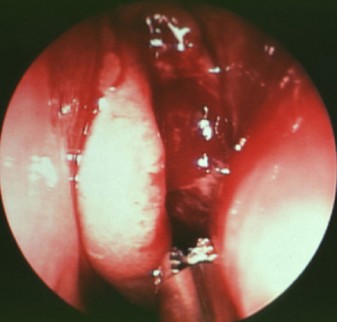

(鼻内窥镜下可见鼻腔息肉肿物、鼻甲肥大)

由几位医生对其进行了专项会诊,很快制定出了详细的手术方案。手术由院长亲自主刀,在鼻内镜下进行了双侧鼻腔息肉摘除术、双上颌窦口扩大、双侧筛窦开放以及双下鼻甲部分切除术,解决了扎西次仁的鼻腔中存在的问题。